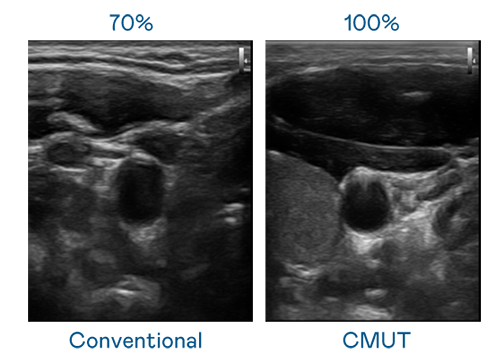

CMUT 技术是一种用电容式微机电元件来产生超音波讯号的技术。与传统 PZT 压电式技术相比,CMUT 频宽增加 30%,更宽频的超音波讯号让影像解析度大幅提升,是实现高影像品质医疗超音波扫描、促进精准医疗发展的关键技术。

大频宽带来超清晰影像

超音波影像的解析度高低,首先取决于探头能发出的讯号频宽。乐竞官网登录入口 CMUT 可提供高清晰的超音波讯号,提供高频宽、高灵敏度、影像纹理细节更高的超音波影像,协助医护人员缩短影像判读时间及利用精准的医疗影像进行诊断。